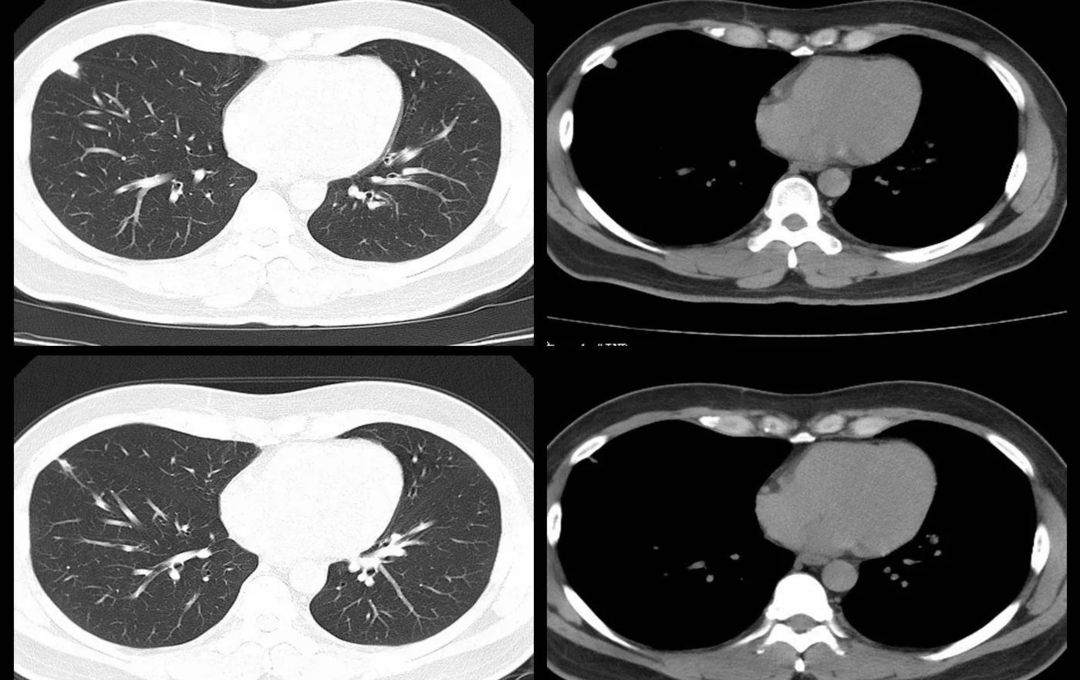

根据结节的密度不同,可以分为纯磨玻璃结节、部分实性磨玻璃结节和纯实性结节。

初次CT检查发现的肺部小结节,80%-90%都是良性病变,但却要高度重视,因为仍有一定比例的早期肺癌,定期检查必不可少。

三、哪些肺部结节恶性可能性大?

通常以下情况肺癌的可能性大:年龄≥40岁且具有以下任何一项危险因素者(肺癌的筛查人群):